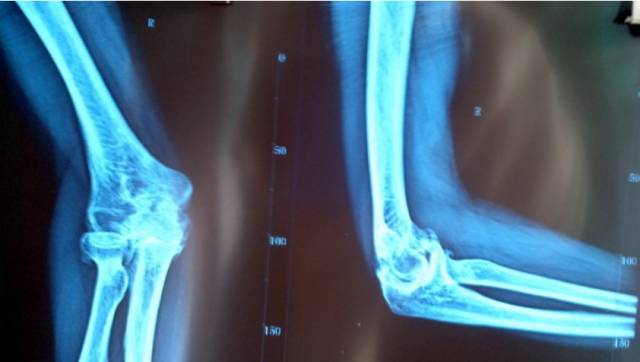

创伤性关节强直的定义:各种外伤、劳损及手术造成的关节活动丧失,固定于某一特定位置,称关节强直,可分为纤维性僵硬和骨性强直两种。

2.外伤性骨性关节强直症

当外伤性纤维性关节强直继续发展, 导致关节骨之同形成骨性连结, 关节功能完全丧失。现代医学除了关节置换,别无他法。而关节置换以后,关节功能并不像医生想象的那样好。

3.相关解剖

由肱骨下端与尺、桡骨上端构成的复合关节, 包括3个关节。

(1)肱尺关节 由肱骨滑车和尺骨滑车切迹构成,属于滑车关节。

(2)肱桡关节 由肱骨小头和桡骨关节凹构成,属球窝关节。

(3)尺桡近端关节 由桡骨环状关节面和尺骨桡切迹构成,属于车轴关节。

3个关节共同包绕在一个关节囊内, 关节囊的前后壁相对松弛. 以关节囊的后壁最为薄弱,两侧壁增厚而且紧张,并有韧带加强。

肘关节的运动功能以成肱尺关节为主,主要在冠状轴上做屈、伸运动,伸前臂时,前臂偏向外侧,构成约为10°的外偏角,称为肘关节提携角。

当肘关节伸直时,肱骨内、外上髁和尺骨鹰嘴三点在一条直线上, 当关节屈曲至90度时, 此三点的连线构成一个尖向下的等腰三角形 。